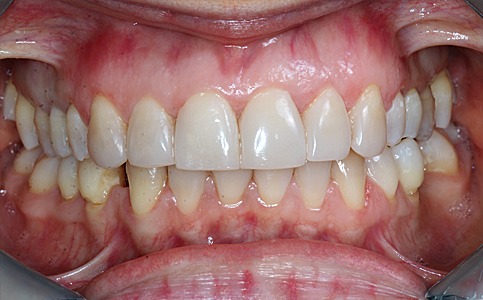

Przykład pełnej rehabilitacji protetycznej obejmujący leczenie biologiczne, uzupełnienie braków zębowych implantami oraz korony pełnoceramiczne w łuku górnym i dolnym. Spektakularna metamorfoza uśmiechu wykonana przez zespół Centrum Stomatologii i Ortodoncji FRESHmed odmieniła życie Pacjenta dodała pewności siebie i sprawiła, że z chęcią się uśmiecha.

Zobacz efekty przeciągając suwak w prawo lub w lewo.